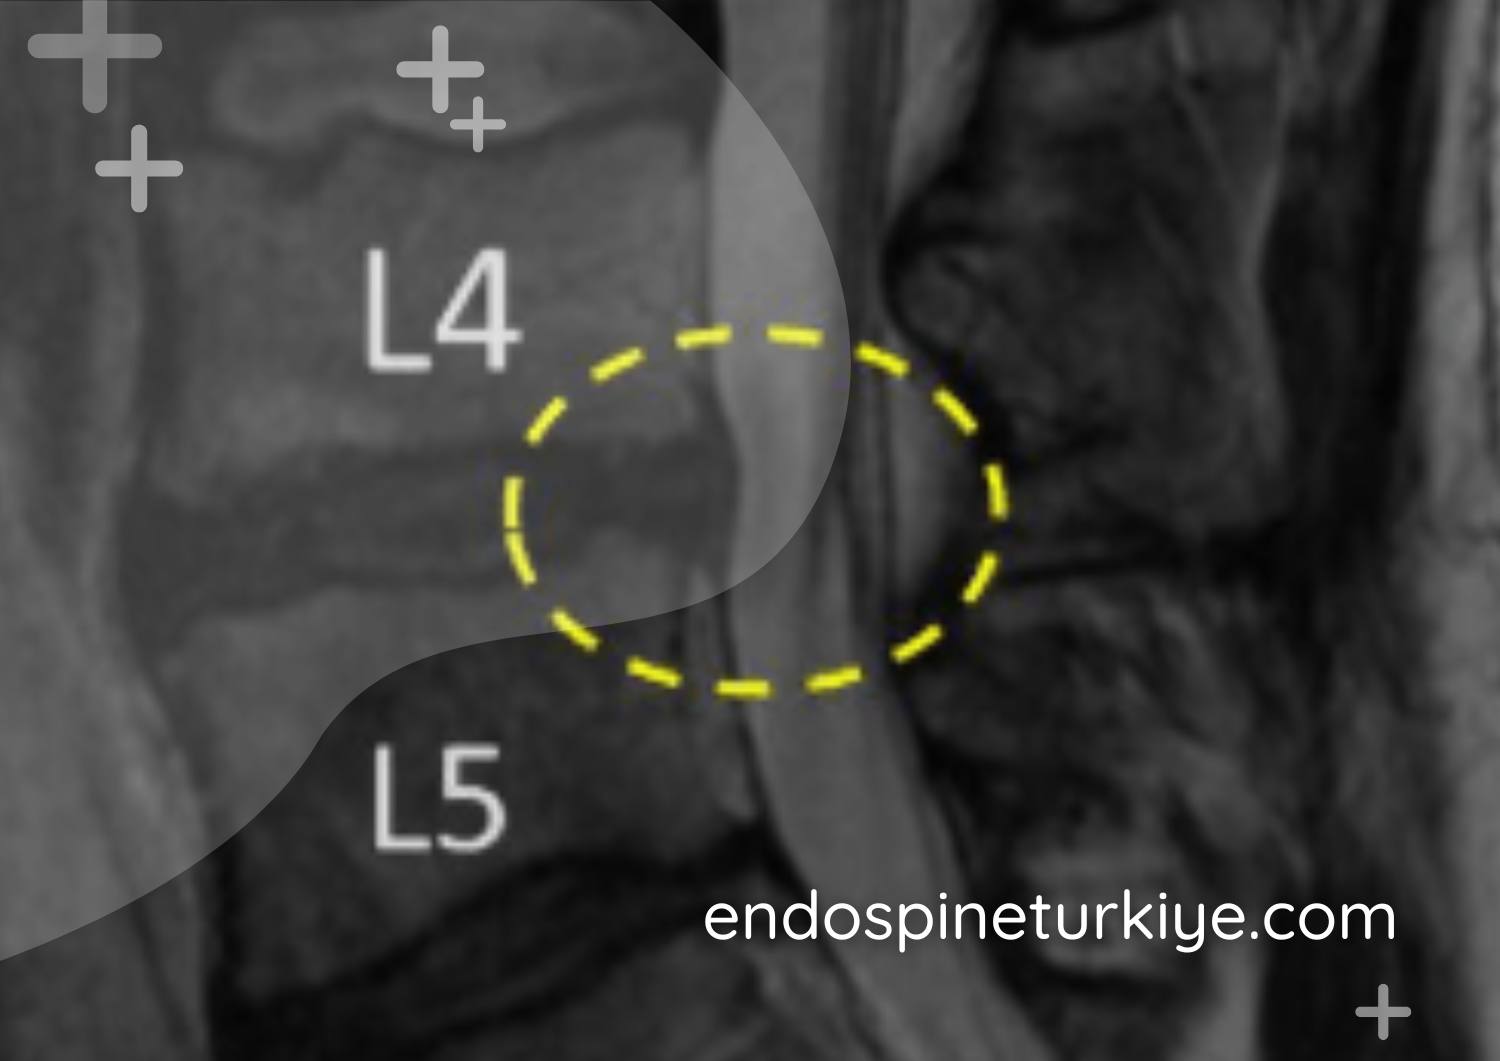

Merkezi Stenoz

Omurga kanalının ortasında meydana gelen daralma. En yaygın karşılaşılan formdur.

Lateral Reses Stenoz

Sinir kökünün geçiş bölgesinde yanal yönde oluşan daralma.